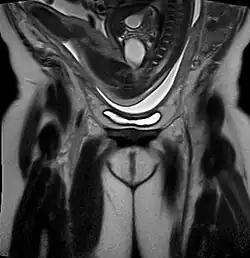

Die Beckenendlage (BEL) ist eine Regelwidrigkeit (Abweichung von der Norm) der Kindslage (Poleinstellung) vor einer Geburt, bei der nicht der Kopf, sondern das Beckenende des ungeborenen Kindes vorangeht. Dabei befindet sich der Kopf des Kindes am Fundus uteri, der Gebärmutterkuppe (oberer Rand der Gebärmutter); das Kind liegt im Mutterleib also mit dem Kopf nach „oben“. Der führende Teil ist der Steiß – daher spricht man von einer Steißgeburt.

Bei der Beckenendlage unterscheidet man je nach der variablen Haltung der unteren Extremitäten zwischen der reinen Steißlage (beide Beine hochgeschlagen) mit 66 % die häufigste Form, der kompletten Steiß-Fuß-Lage (beide Beine angehockt) und gemischten Formen (nur ein Bein hochgeschlagen, Knielagen, Fußlagen).